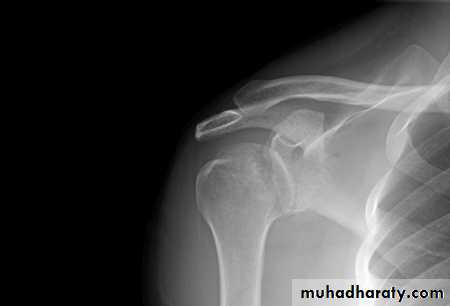

Sensation cannot be tested in a baby.X-rays

should be obtained to exclude fractures of

the shoulder or clavicle (which are not uncommonand which can be mistaken for obstetrical palsy).